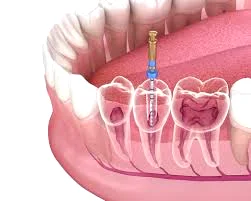

برای درک درد بعد از عصبکشی، ابتدا باید بدانیم در این درمان چه مراحلی طی میشود.

درمان ریشه یا عصبکشی زمانی انجام میشود که پالپ دندان (بافت نرم داخل دندان شامل عصب و عروق خونی) دچار التهاب یا عفونت شده باشد. در این فرآیند:

- عصب و بافت ملتهب از داخل کانالهای ریشه خارج میشود

- کانالها بهطور کامل شستشو و ضدعفونی میشوند

- فضای خالی با مواد مخصوص پر میشود

هرچند عصب دندان برداشته میشود، اما بافتهای اطراف ریشه (استخوان و لیگامانهای اطراف) همچنان زنده هستند و میتوانند به تحریک یا فشار واکنش نشان دهند.